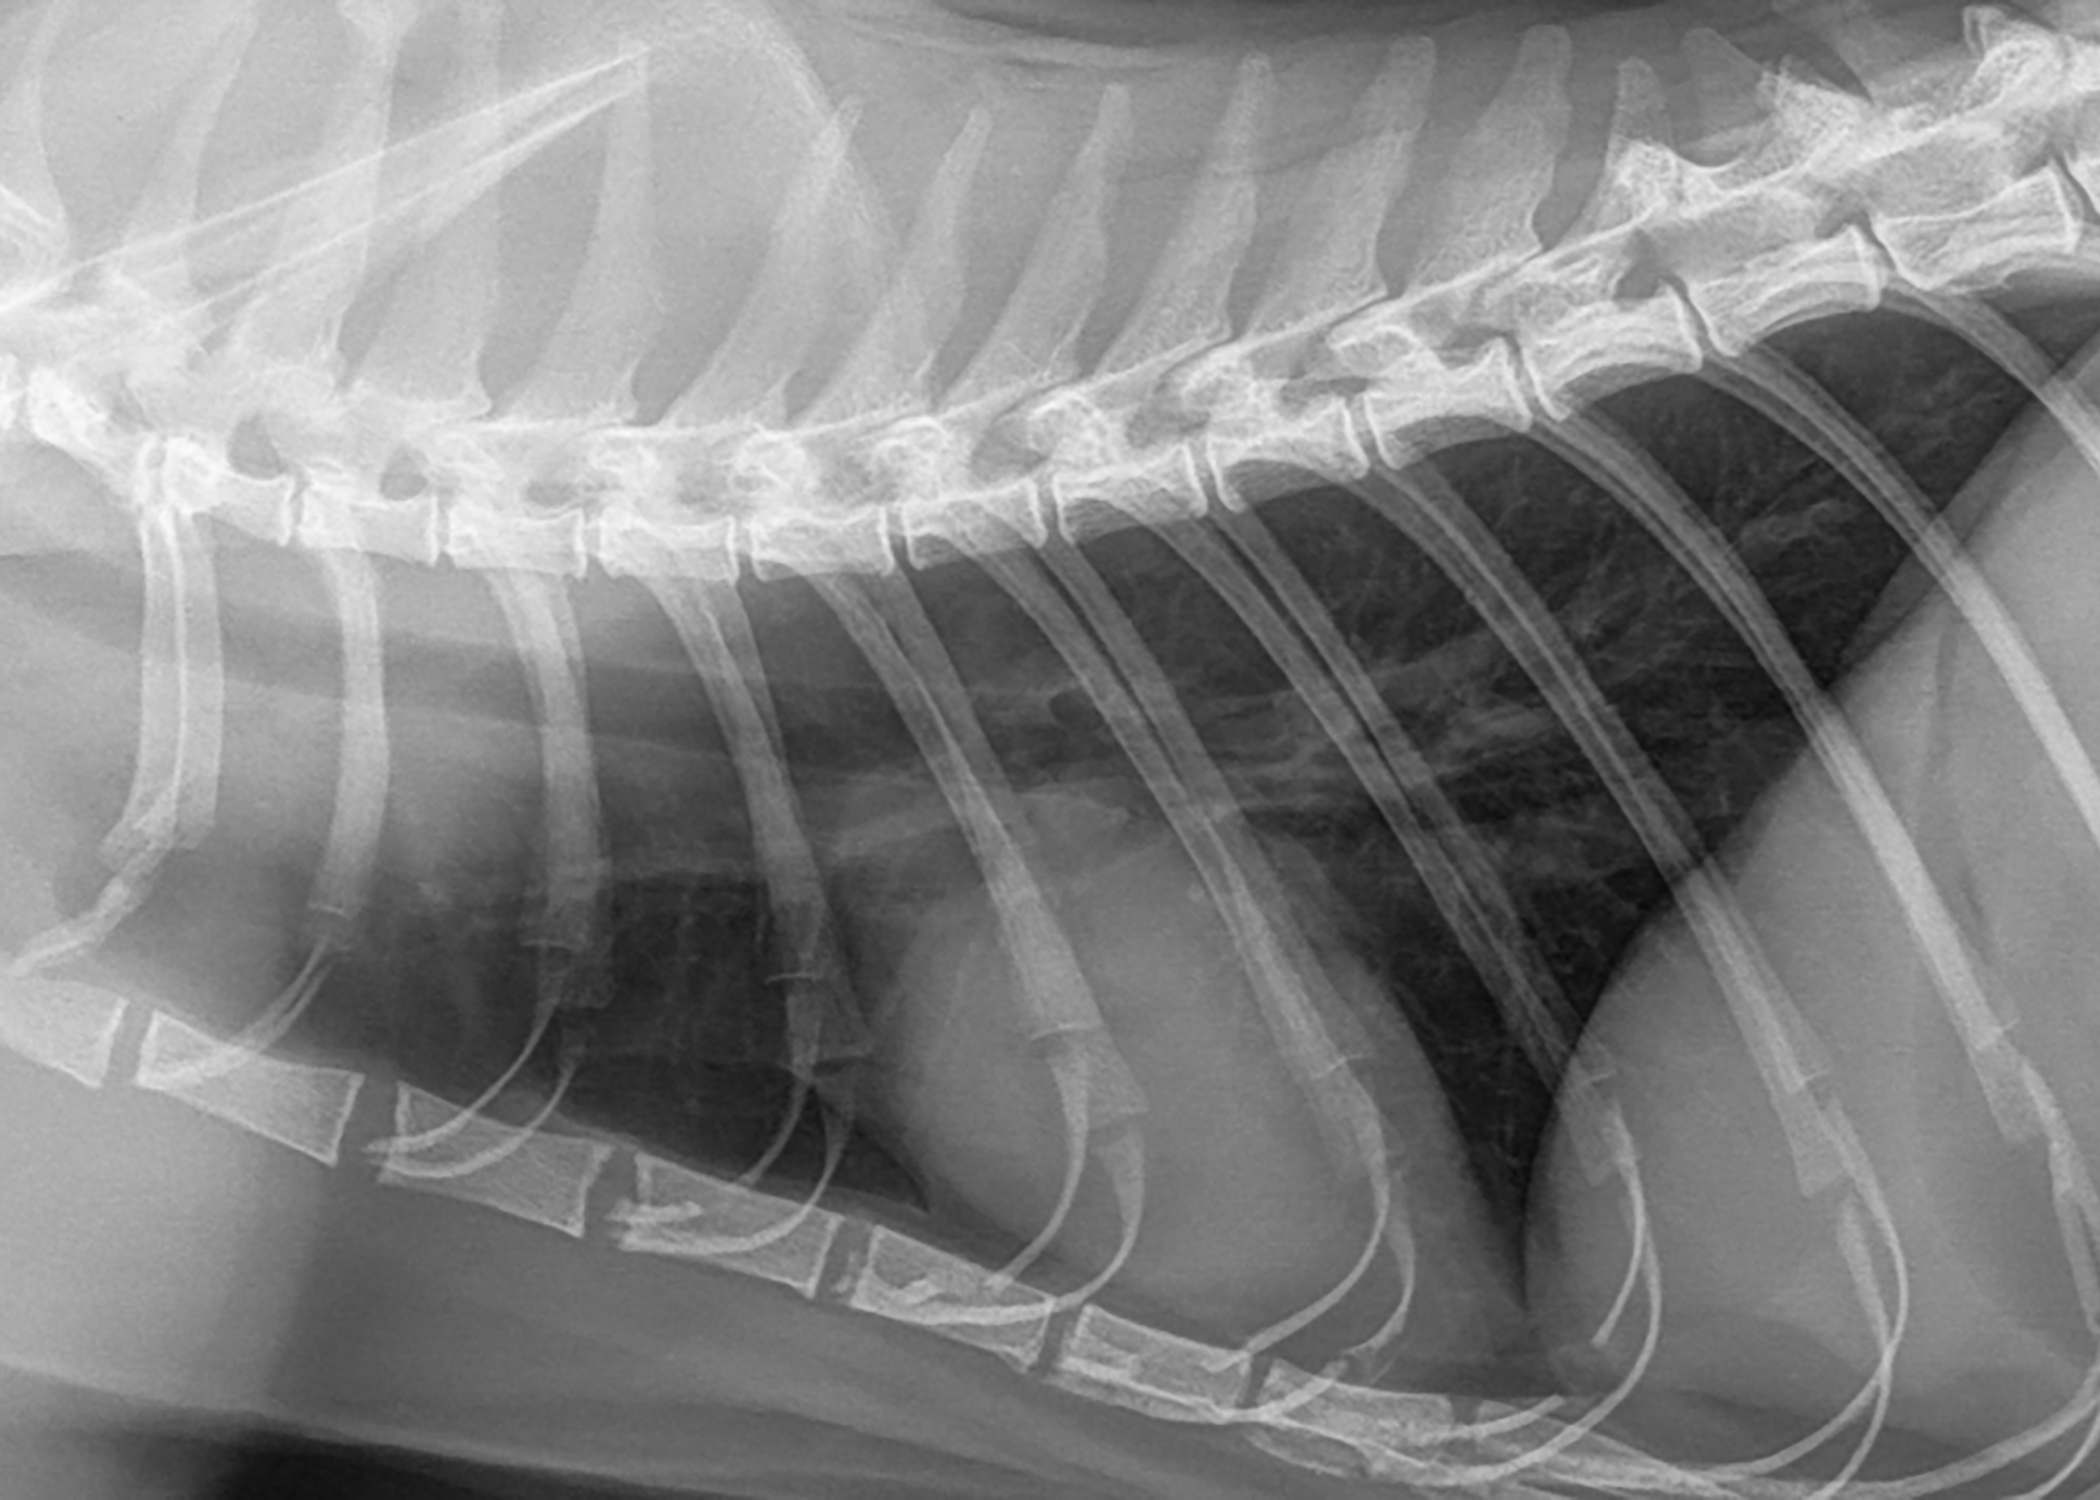

Interpreting thoracic radiograph lung patterns VETgirl Veterinary Cat Lung X Ray Difficulty breathing (dyspnea), rapid breathing (tachypnea), lethargy, poor. To evaluate respiratory conditions like asthma, bronchitis, and pneumonia, heart conditions, broken ribs, and. Lung cancer in cats is a topic that many pet owners may find concerning. The diagnosis is similar to that for primary lung tumors. The top red arrow points to the aorta. Pulmonary disease usually results in either. Cat Lung X Ray.

Xray of a Cat with Advanced Asthma with Pneumonia, Extensive Bronchial Cat Lung X Ray Lung cancer in cats is a topic that many pet owners may find concerning. Pulmonary disease usually results in either an increase or a decrease in radiographic opacity of the lungs. The bottom red arrow points to the. Difficulty breathing (dyspnea), rapid breathing (tachypnea), lethargy, poor. Most diseases result in an. To evaluate respiratory conditions like asthma, bronchitis, and pneumonia,. Cat Lung X Ray.

Lung; cat No. 1. Diffuse, severe bronchointerstitial pattern Cat Lung X Ray Lung cancer in cats is a topic that many pet owners may find concerning. Difficulty breathing (dyspnea), rapid breathing (tachypnea), lethargy, poor. While the incidence is relatively low compared to other feline diseases, the seriousness of a lung cancer diagnosis cannot be underestimated. To evaluate respiratory conditions like asthma, bronchitis, and pneumonia, heart conditions, broken ribs, and. Pulmonary disease usually. Cat Lung X Ray.